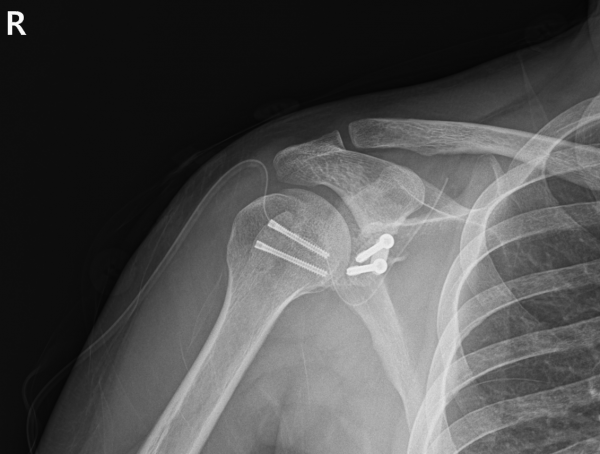

Headless Screw 2개로 고정

안정적이고 생역학적으로 유리한 고정을 위해 headless screw를 사용했습니다.

Open Latarjet 시행

부리돌기를 조심스럽게 떼 내어 관절와 결손부위에 이식하여 관절 전방의 구조적 안정성을 확보했습니다.

이 술기가 병합되어야만 재탈구 위험을 실제로 줄일 수 있었습니다.

전체적으로 정밀성이 요구되는 고난도의 술기였고,

수술은 계획한 대로 잘 마무리되었습니다.

수술 후 첫 CT 결과에서 이식된 상완골두는 정렬 상태가 매우 우수하고, 결손 부위를 정확하게 메우고 있었습니다.

부기·염증수치·통증 모두 양호했고, 신경학적 문제 없이 손·손가락 운동도 잘 되었습니다.

환자는 8일 후 안정적으로 퇴원했고, 현재 외래 추적에서도 회복 경과가 좋습니다.